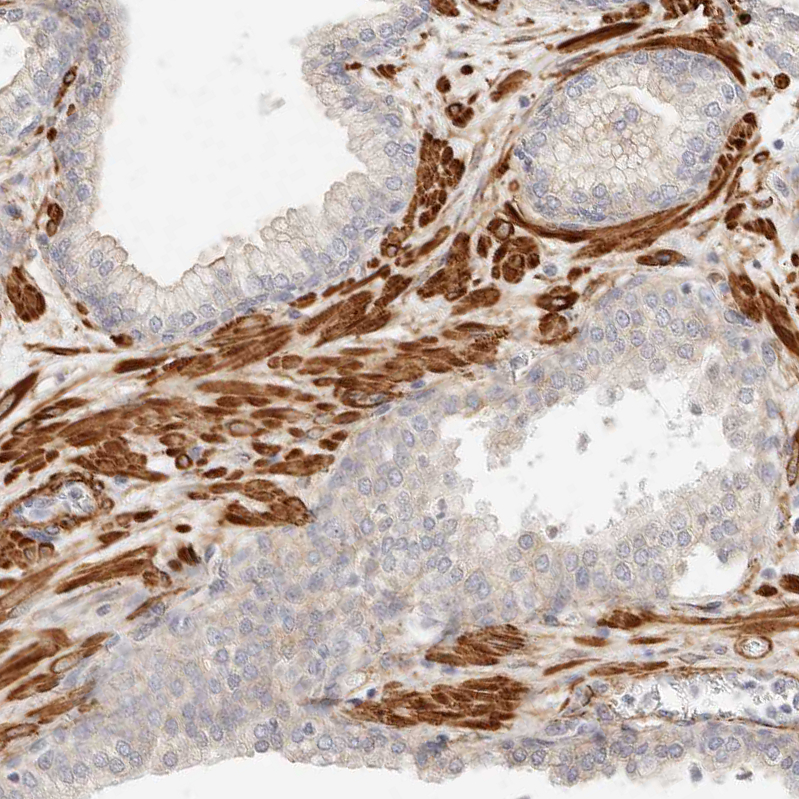

Immunohistochemical staining of human fallopian tube shows strong cytoplasmic positivity in stromal cells.